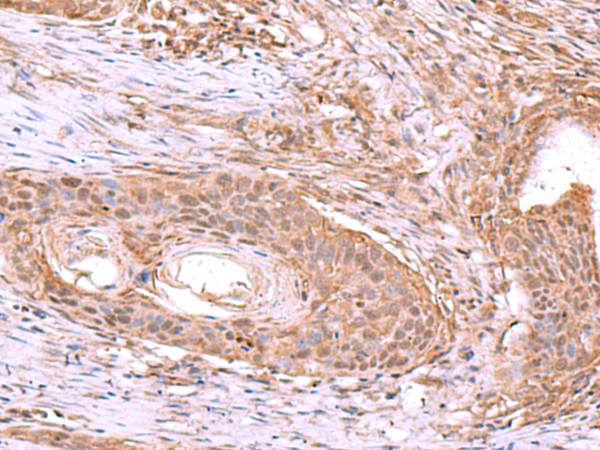

分类: 科研抗体货号: P06767别名: ISM; Isthmin; C20orf82; bA149I18.1; dJ1077I2.1应用: WB,IHC反应种属: Human, Mouse